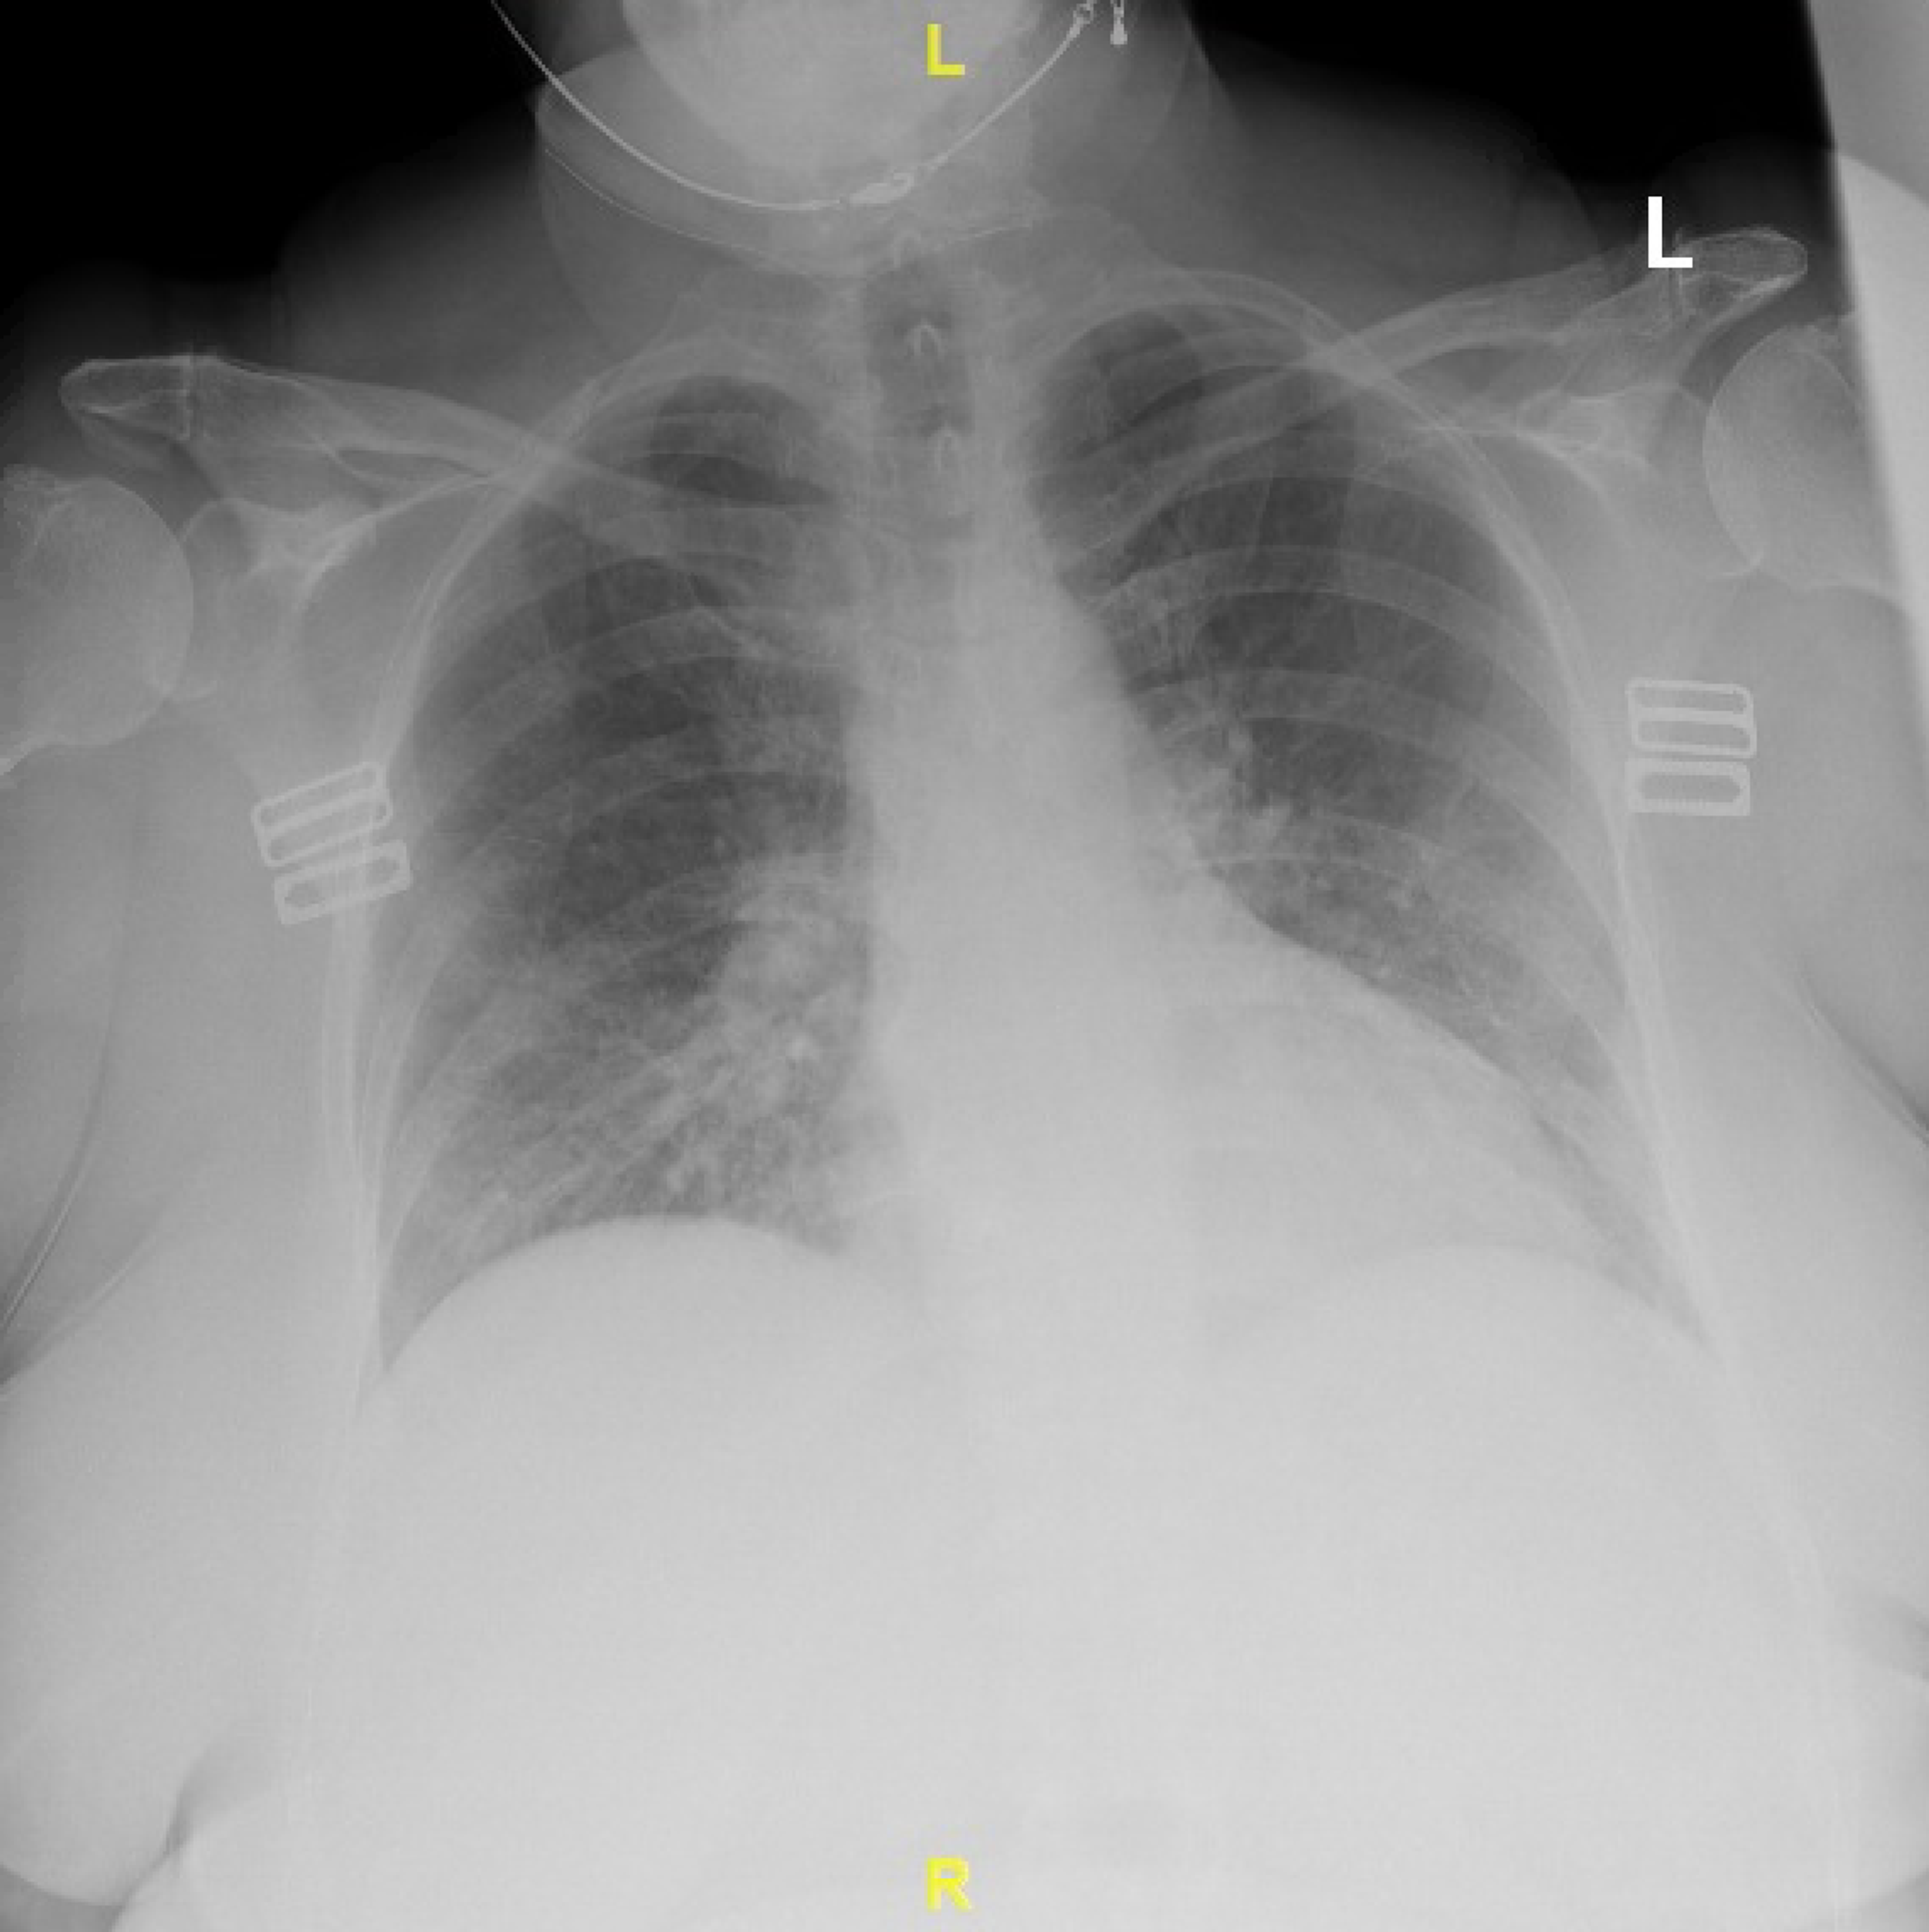

Cureus Concurrent Diagnosis of Acute Myeloid Leukemia and COVID19 A Chest X-Ray To Diagnose Leukemia It is used to look for: — myeloid sarcoma. — physical exams for diagnosing leukemia. If the scan finds an abnormal. Consider seeking medical care if you have developed any of these. Although the thorax is uncommonly involved, it may occur in the lungs, pleura, mediastinum, chest. a ct scan of the chest or abdomen can help. Chest X-Ray To Diagnose Leukemia.

From www.cureus.com